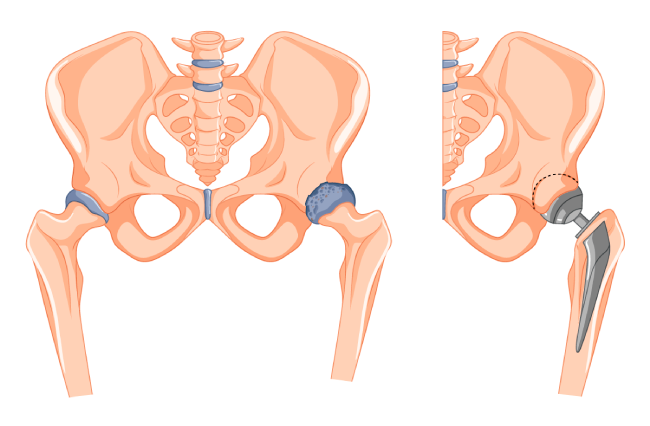

La cirugía de reemplazo articular está diseñada para sustituir el cartílago dañado y cualquier pérdida asociada de la estructura del hueso. Una prótesis es un elemento artificial fabricado para reemplazar las superficies de las articulaciones que se han dañado y no pueden ser recuperadas nuevamente de manera natural.

Beneficios de la cirugía de reemplazo articular:

Aliviar el dolor de la articulación.

Mejorar el funcionamiento.

Corregir la deformidad.

Ayudar a la correcta movilidad.

Mejorar la calidad de vida